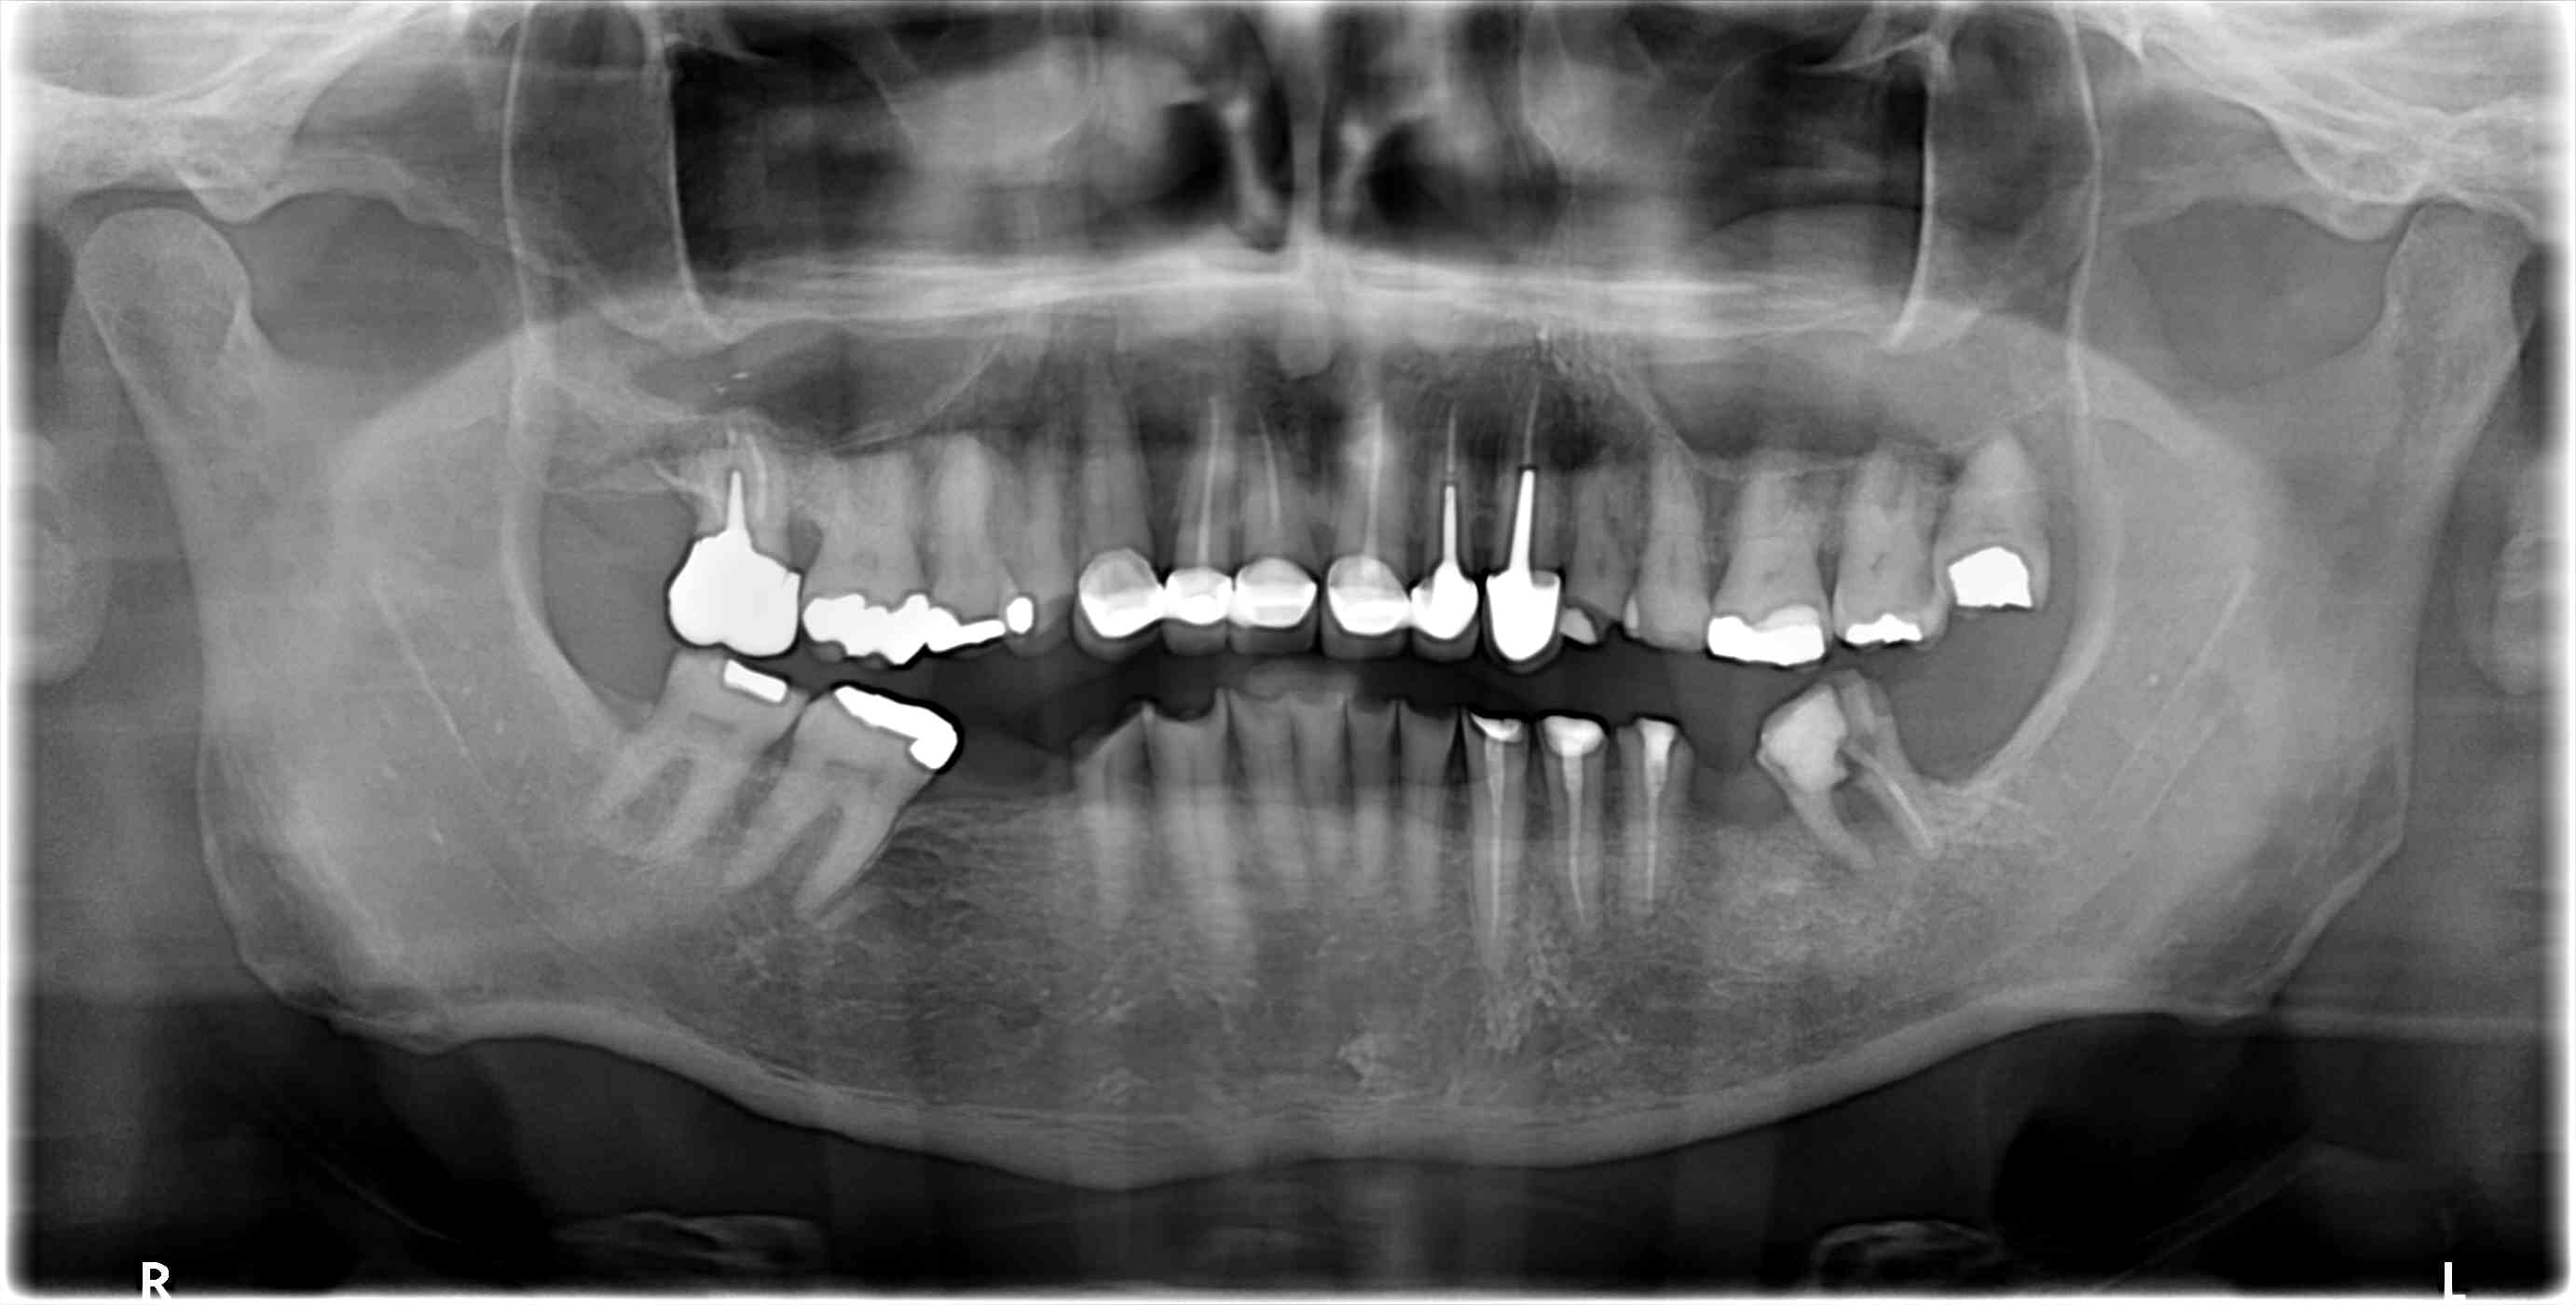

Ce patient se présente à moi pour poser 3 implants, et si possible redonner un peu d'esthétique à son sourire car ses incisives du bas sont trop "petites".

Je lui ai proposé d'extraire avant toute chose la 37 qui est condamnée et qui fausse l’étude de l’occlusion (en demandant de serrer je n'ai qu'un contact sur la 47 et la 37 (qui est algique et qui provoque un réflexe d'évitement). Vu les usures massives, je doute d'avoir qu’une composante erosive (ROG probable). Mais je préfère adresser pour la suite, n'ayant qu'une maigre expérience de ce genre de cas. Je connais dans les grandes lignes la théorie d'approche de ces plans de ttt (rehausser et tester la DVO avec une gouttière, puis des mock up et enfin des restaurations céramique collées type facette et table top) mais je n'en ai jamais réalisé.

Si tu lui enleves la 37 , tu pourras constater que la couronne de 17 ne va pas bien .

Il doit y avoir un decalage lateral dessus à tous les coups .

Tout ceci a été augmenté ou causé par un sur contact ant . Je dis ca pcq 13 12 11 ont ete faites sans reconstitutions , donc il y avait encore de la matiere . Pour solidariser je pense , à demander . C est donc qu il y avait deja dessus une parafonction d evitement de derriere .

Si la 17 est en fer ce serait elle la salope .

Si c est du zircon elle est plus recente et elle a du etre calée dans l occlusion deja pipée .

voila pourquoi je dis qu elle ne doit pas etre top dans tous les cas.

Et voila aussi pourquoi je dis tjs qu il faut tjs essayer de connaître l ordre des travaux deja effectués . pouvoir expliquer le passé permet d envisager l avenir . En tout cas c est plus facile de poser un diag sur la direction du calage a rechercher .

Très intéressant ton analyse comme toujours. De souvenir oui la 17 est en ferraille et bien ancienne

Les CR du bloc antr sup sont à étudier avec attention je pense.